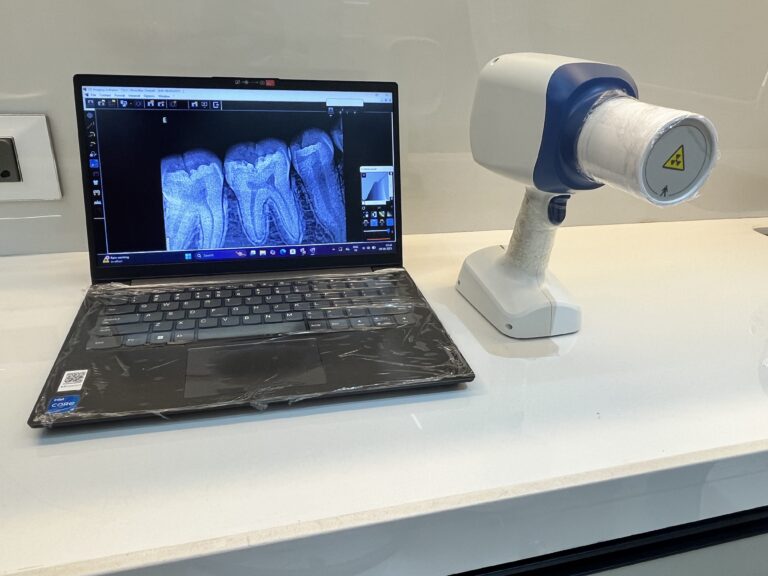

Our portable X-ray unit allows us to quickly capture diagnostic images during your consultation, ensuring faster evaluations and seamless treatment planning. Whether it’s for detecting cavities, assessing root conditions, or evaluating bone health, our X-ray facility ensures accuracy without delay.

With zero need for repositioning or multiple visits, patients enjoy a more comfortable, time-saving experience while our team gets the detailed data needed for expert care.